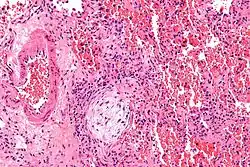

| Micrograph showing a Masson body (off center left/bottom of the image – pale circular and paucicellular), as may be seen in cryptogenic organizing pneumonia. The Masson body plugs the airway. The artery associated with the obliterated airway is also seen (far left of the image). H&E stain. | |

Histologically, cryptogenic organizing pneumonia is characterized by the presence of polypoid plugs of loose organizing connective tissue (Masson bodies) within alveolar ducts, alveoli, and bronchioles.